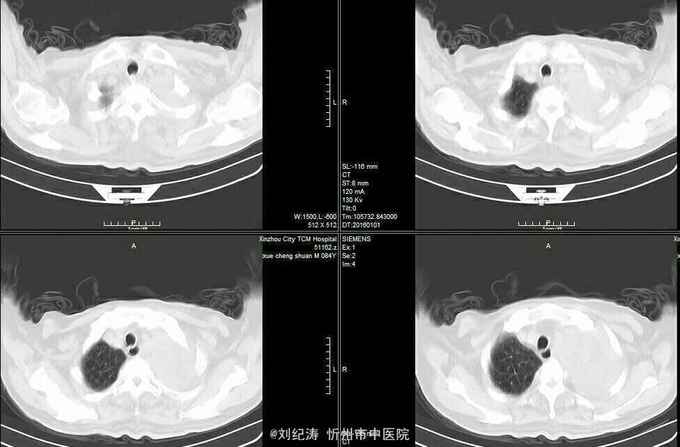

查体:ECOG评分:3分,生命指征平稳,浅表淋巴结未触及明显肿大,双眼睑无水肿,唇无发绀,颈软,双侧胸廓对称,左肺语颤增强,左肺呼吸音消失,右肺呼吸音粗,可闻及哮鸣音,心律齐,腹平软,肝脾肋下未触及,移动性浊音阴性,肠鸣音3次/分,双下肢无水肿。 辅助检查:血常规(2016.1.1):WBC:10.6*109/L,RBC:4.69*1012/L, PLT:165*109/L ,HGB:167g/L.生化(2016.1.1):谷丙转氨酶11U/L,谷草转氨酶11U/L,总蛋白60g/L,白蛋白33g/L,尿素:9.8mmol/L,肌酐:123umol/L,尿酸:251 umol/L,血糖:7.37 mmol/L;电解质:钾:4.79mmol/L,钠:123.5 mmol/L,氯:85.7 mmol/L,钙:2.03 mmol/L。肺部CT(2016.1.1):左肺完全萎缩,左侧胸腔大量积液,右肺未见异常,纵膈轻度右移,未见明显肿大淋巴结。